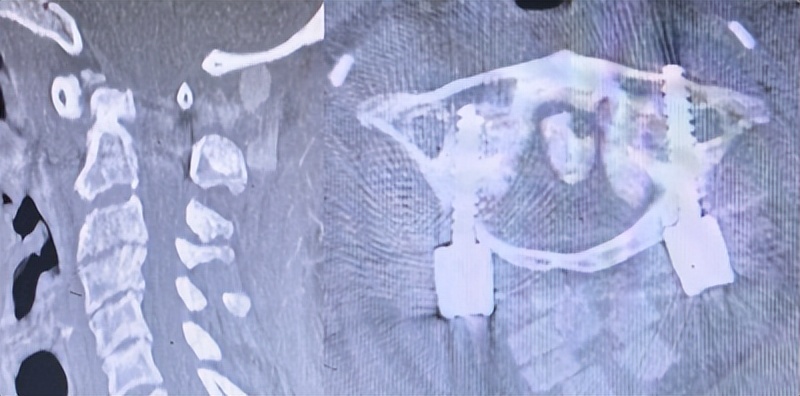

雷女士家属带她来到了西安市红会医院脊柱病医院颈椎病区就诊,门诊影像学检查显示,患者存在寰枢椎关节严重脱位,伴有游离齿状突,同水平椎管严重狭窄,并已出现脊髓缺血性改变,齿状突与寰椎后弓之间的间距仅占椎管直径的13.2%。

面对这一高难度、高风险病例,王彪主任医师团队在充分评估和多轮术前讨论后,毅然决定迎难而上。整个手术过程顺利,成功实现寰枢椎完全复位。影像显示,齿状突与寰椎后弓间距扩大至椎管直径的46.2%,脊髓容积较术前增加约2.5倍。患者术后恢复良好,四肢麻木感及肌力明显改善,术后第3天即在家属协助下实现下地行走,摆脱了对轮椅的依赖。